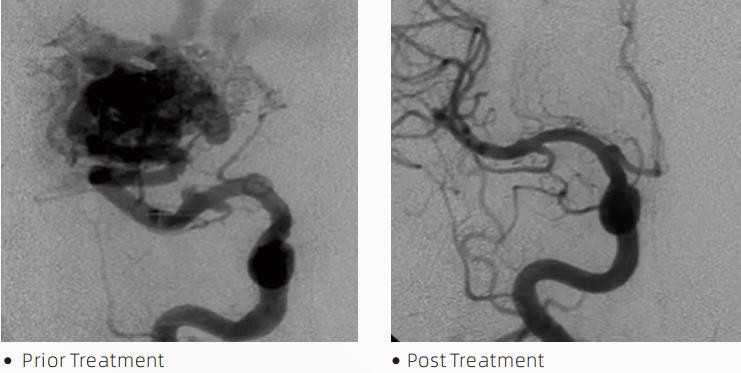

LavaenTMLiquid Embolic System er en intervensjonell endovaskulær terapi for behandling av cerebrovaskulære misdannelser. Cerebrovaskulær misdannelse refererer til en gruppe godartede eller ondartede nevrovaskulære abnormiteter som kan føre til intrakraniell blødning, hjerneinfarkt, cerebral iskemi og andre sykdommer. Det flytende emboliseringssystemet er et medisinsk utstyr som administreres gjennom enkel intravaskulær innsetting, som emboliserer unormale cerebrale blodårer ved å injisere et spesielt væskemateriale. Det flytende materialet danner en kontrollert vevsemboli i blodårene, noe som kan redusere virkningen av cerebrovaskulære misdannelser på pasienter. Et DMSO-kompatibelt leveringsmikrokateter som er indisert for bruk i nevrovaskulaturen, brukes for å få tilgang til emboliseringsstedet. Lava flytende embolisk middel er et ikke-klebende flytende embolisk middel som består av EVOH (etylenvinylalkohol) kopolymer oppløst i DMSO (dimetylsulfoksid), og suspendert mikronisert tantalpulver for å gi kontrast for visualisering under fluoroskopi. LavaTMer tilgjengelig i tre produktformuleringer, LAVA-12, LAVA-18 og LAVA-34. LAVA-12: Anbefales ved mating av distale mikrokar og gjennom små matere. LAVA-18: Anbefales når fôring av pedicle injeksjoner vil bli utført nær nidus; LAVA-34: Anbefalt for embolisering av høyere flyt og større fistulære komponenter.